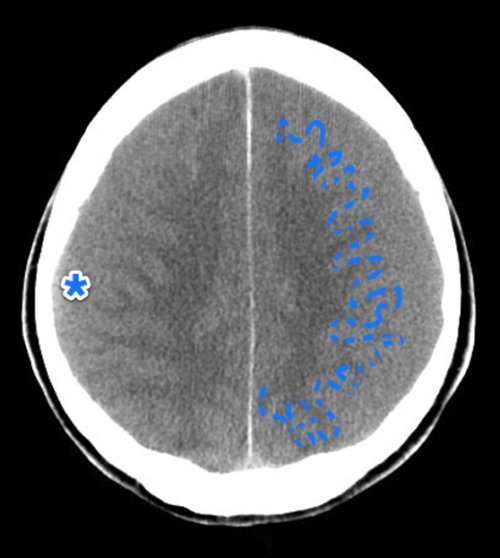

27- في بقي نوع خبيث بتلاقي كل الcistern مفتوحة زلفل بس في الsulcus تحت بقي فيه خط ابيض ، او نقطة دم في قاع الlateral venrticles

لو مش عينيك في وسط راسك سهل جدا انك تmiss عيانSAH

لازم تتاكد ان كل الcisterns - ventricles والsulci مفتوحة وفيها csf اسود

28- ع الناحية التانية ، في ناس بتتلخبط بين calcification الdura وتقول عليه دة دم جوا الcistern

وناس اروش بتتلخبط بين الcalcification بتاع الchoriod plexus وتقول عليه دم جوا الventricles

انا قعدت شهور عشان اتقن منظر الsubarachnoid في الاشعة

- venous sinus thrombosis